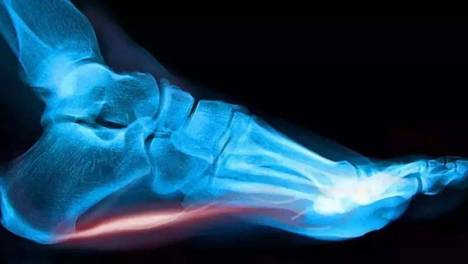

脚底板长的这个是老茧还是鸡眼?小心还有可能是跖疣!